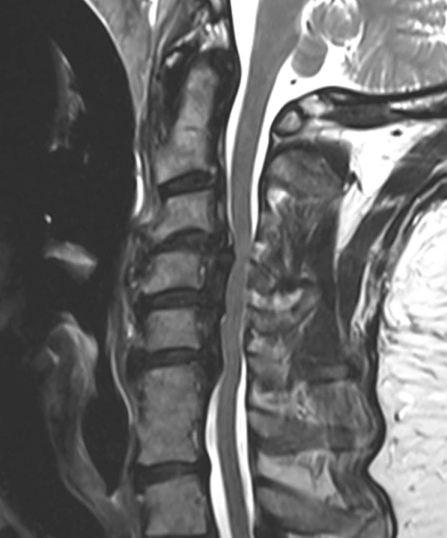

OPLL을 진단하기 위해 의료 서비스 제공자는 일반적으로 철저한 신체 검사와 증상 검토부터 시작합니다. X선, MRI, CT 스캔과 같은 영상 검사는 인대 골화의 존재를 확인하고 척추관과 신경에 미치는 영향을 평가하는 데 중요합니다.